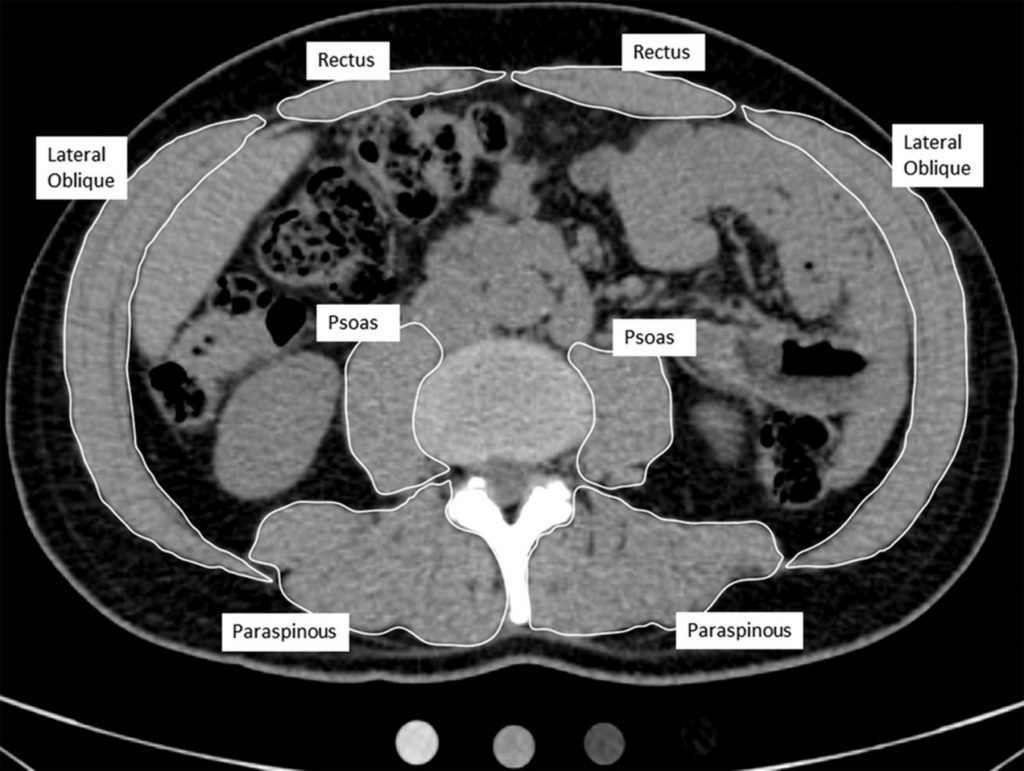

(post destacado 2018) El tejido adiposo intermuscular (IMAT) se acumula con la edad. No sabemos que un ejercicio como caminar […]